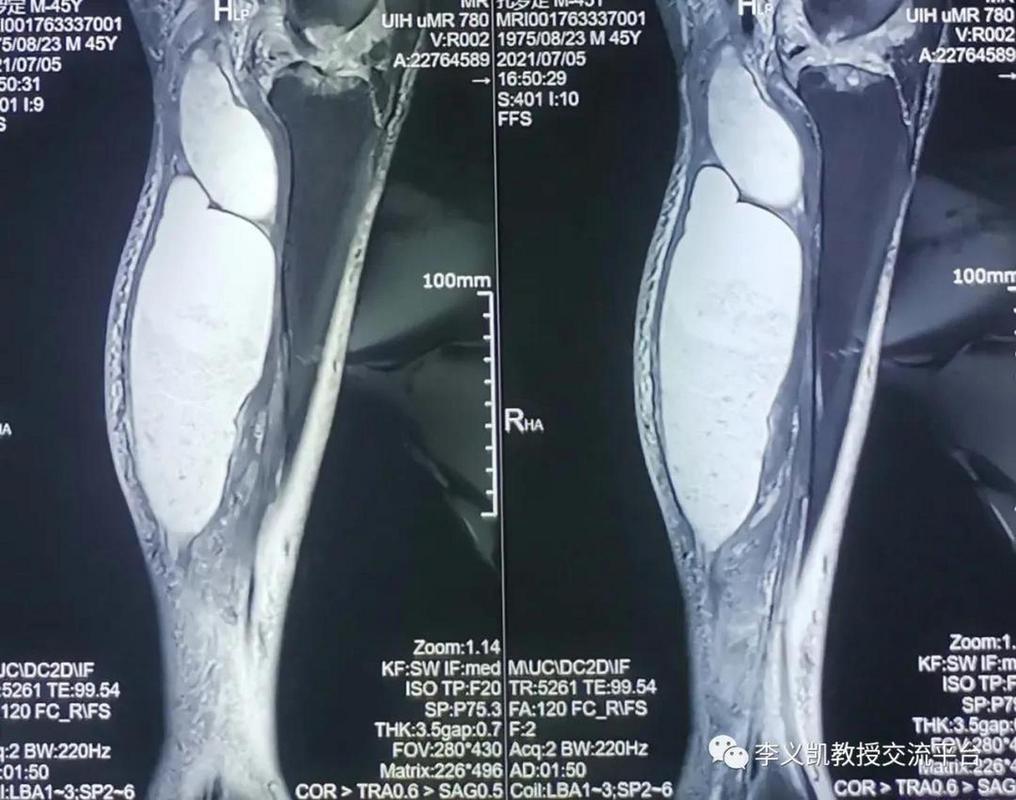

核磁共振能检查类风湿

(图片来源网络,侵删)

核磁共振能检查到类风湿的什么?

类风湿关节炎是一种以滑膜炎症为特征的自身免疫性疾病,核磁共振通过其强大的软组织成像能力,可以直接观察到X光片无法显示的早期病理改变:

1. 滑膜炎

• 这是类风湿关节炎最核心、最早期的病变。 MRI可以清晰地显示关节内滑膜的增厚、肿胀和异常信号,通过特殊的对比剂(钆剂)增强扫描,增生的滑膜会明显强化,这是诊断早期RA的关键依据。

2. 骨髓水肿

在MRI图像上表现为骨骼内部出现片状、边界不清的高信号区,它被认为是关节炎症和损伤非常早期的标志,预示着骨质破坏即将发生,骨髓水肿的存在与疾病的活动性和未来骨侵蚀的风险高度相关。